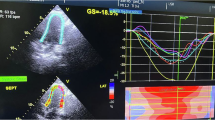

Before the hemodialysis session, standard echocardiographic measurements were obtained from the left parasternal and apical views according to the recommendations of the American Society of Echocardiography,18 using an ALOKA alpha 10 ultrasound system (Aloka, Tokyo, Japan). The LV end-diastolic dimension, LV end-systolic dimension, interventricular septum thickness and posterior wall thickness were determined using standard echocardiographic 2D measurements. The left atrial volume (LAV) was measured using the biplane method of discs incorporating both apical 4- and 2-chamber views. The LV mass (LVM) was determined using the 2D area-length formula. LAV and LVM were indexed to the body surface area as the LAV index (LAVI) and LVM index (LVMI), respectively. The ejection fraction was calculated by the modified Simpson method. The transmitral inflow was recorded using pulsed wave Doppler recordings at the mitral valve leaflet tips in the apical 3-chamber view. The peak early diastolic filling velocity (E), peak late diastolic filling velocity (A), E/A ratio and deceleration time of the E wave were measured. The tissue Doppler image program was set to the pulsed wave Doppler mode, and sample volumes were positioned at the septal corner of the mitral annulus.19 Then, we measured the early diastolic mitral inflow velocity and calculated the ratio of E over E′ (E/E′) to represent LV filling pressure.20

The relationship between the ratio of OPG to fetuin-A, baPWV (a), AOCS (b), LAVI (c) and E/E′ (d) in all 63 subjects. The ratio of OPG to fetuin-A correlated significantly and positively with the baPWV, AOCS, LAVI and E/E′. A full color version of this figure is available at the Hypertension Research journal online.